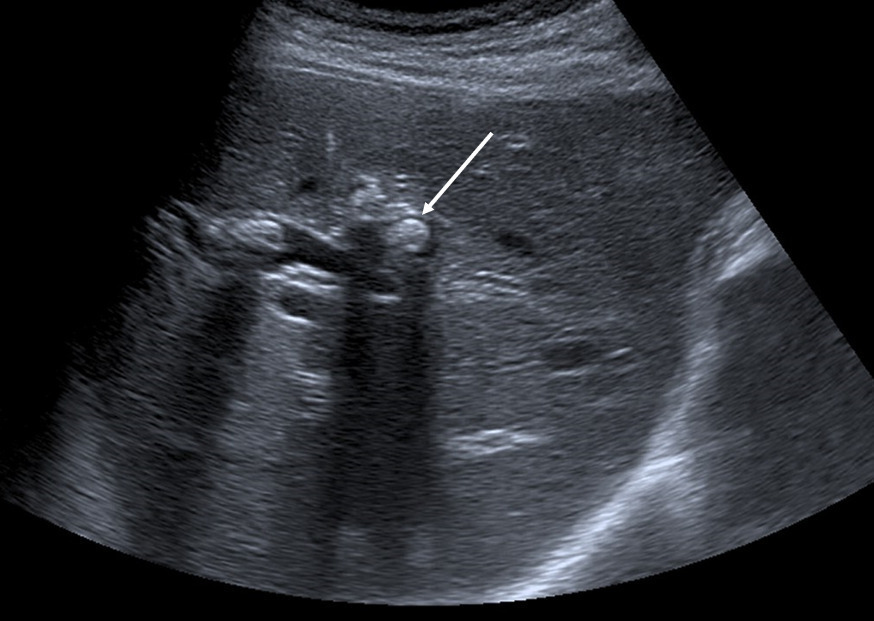

La cholécystectomie doit être évitée dans la mesure du possible car elle ne prévient pas le risque de récidive d’événement biliaire, qui est lié, dans la très grande majorité des cas, à la lithiase intrahépatique et non à la lithiase vésiculaire. La lithiase vésiculaire n’est présente que dans 30 % des cas de syndrome LPAC. En revanche, en cas de cholécystite aiguë lithiasique avérée, la cholécystectomie doit bien sûr être réalisée afin de limiter le risque de complications (perforation, abcès, péritonite). Une hépatectomie partielle peut être proposée en cas d’empierrement des voies biliaires intra­hépatiques, symptomatique ou compliqué (angiocholites, abcès) et en cas d’échec du traitement par AUDC, si cet empierrement est limité à un lobe ou à un segment du foie (fig. 3).